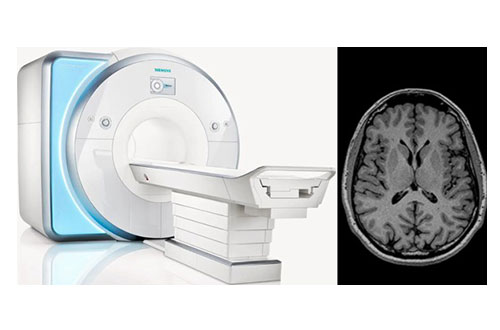

정밀 뇌검사의 표준, 놓치지 않는 이상 징후 뇌 MRI

뇌 MRI는 뇌졸중, 뇌종양, 치매 등 다양한 뇌 질환을 고해상도로 진단하는 가장 정밀한 뇌 영상 검사입니다.

대학병원급 MRI 장비를 활용해 미세한 이상까지 놓치지 않고 진단합니다.

뇌혈관의 흐름을 읽어내는 비침습적 혈관 검사 두경부 MRA

두경부 MRA는 자기공명 혈관조영술(Magnetic Resonance Angiography)로 뇌와 경부(목) 혈관의

협착, 폐색, 기형 등을 선명하게 파악할 수 있는 검사입니다.

조영제를 사용하지 않아 몸에 부담이 적고, 뇌졸중 예방에도 효과적입니다.